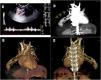

Complex pulmonary arteriovenous malformation (AVM) in the right middle lobe in a boy aged 18 months. (A) Thoracic POCUS with a stronger Doppler signal along the right thoracic wall at the level where a murmur was heard on auscultation. (B) CT angiogram showing the pulmonary AVM (arrowheads). (C and D) 3D reconstruction of CT scan provides both anterior and posterior views of the intricate pulmonary AVM, illustrating its complexity.

A CT angiogram revealed a arteriovenous malformation (AVM) in the right middle lobe (Fig. 1, panel B-D). The family history was suggestive of hereditary haemorrhagic telangiectasia (HHT), and abdominal and brain imaging showed no vascular anomalies. Embolization with a nitinol vascular plug improved oxygen levels. Genetic testing is underway.